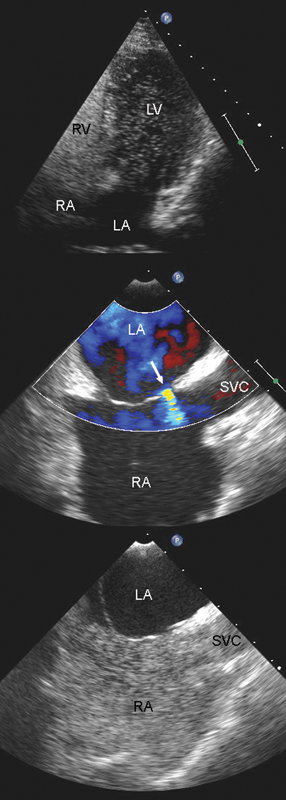

فحوصات تشخيصية لبعض امراض القلب والشرايين التاجية